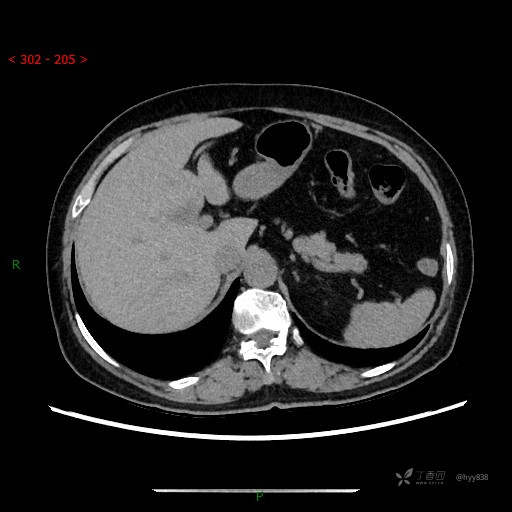

讨论:病变性质?

静脉期